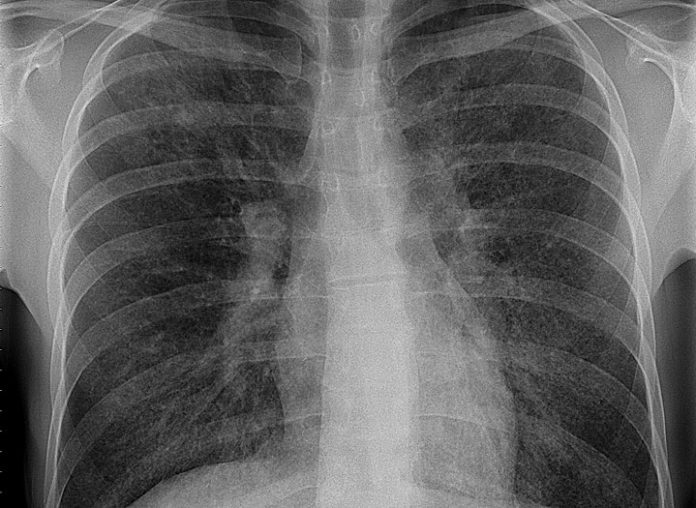

Mniejsza z tą panią. Wykonałem tomografię płuc w wysokiej rozdzielczości. Wyszedł i miód, i cud, na mlecznej szybie ryba z kitem wyszły, przez szybę zaś siateczki, plastry oraz inne, rozmaite obszary. Co do obecności pszczół pewności nie uzyskałem. Się wyroją, się ewentualnie zobaczy – w każdym razie dziś brzęczy we mnie wyraźniej niż wczoraj. A tu podsumowanie badania: “Zmiany w płucach o radiologicznym wzorcu prawdopodobnego UIP o niewielkim nasileniu (15-20%)”. Obraz radiologiczny moich ukochanych acz niedomagających płuc otrzymałem więc niecharakterystyczny, mimo obecności charakterystycznych zmian dla płuc wątpiących. Włókniejących, znaczy. Czyli co robić? Nic. Nadejdą zmiany, się uwidocznią, za charakterystykę zmiany złapiemy, odpowiednio przesłuchamy.